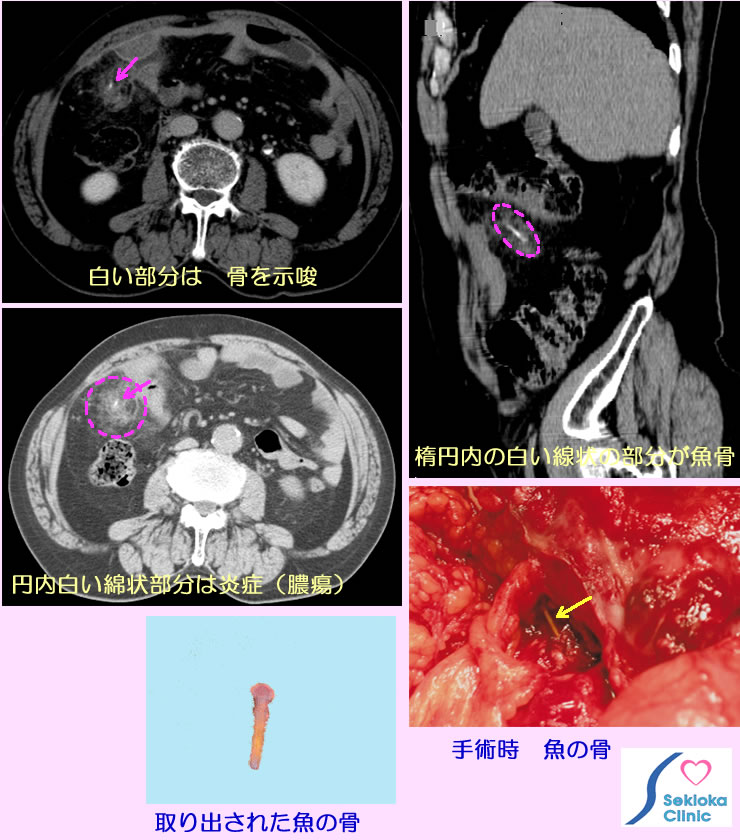

| 診断 | 自覚症状、腹部の触診から腹膜炎の可能性を推定し、超音波エコー検査、CT検査を行います。腹部全体を見逃しなく検査するにはCTが適しています。より詳細にはMDCT。添付画像は腹痛で来院。回盲部腹壁を押さえると痛みがあり、MDCTで検査。上段左画像では回盲部に白く表示されるX線吸収値の高い異物を認め、その周囲は綿毛のように見え、炎症を疑います。右画像はMDCT3次元画像から、その白く描出された部分を詳細に調べるため適切な断面画像を設定して画像化したもので その異常部分は針状に長く、X線吸収値から魚の骨である疑いがもたれます。開腹手術にて下段写真に見られるような1cmの長さの魚骨が大腸の腸管壁に刺さり化膿して腹膜炎を起こしたものであることが確認されました。腹膜炎は潰瘍の穿孔、いろいろな炎症の腹壁への波及、腸閉塞と腸管壁の壊死、がんの腹壁転移(がん性腹膜炎)など多くの原因で生じます。魚の骨のような小さな異状を検索するには MDCTが適しています。 |